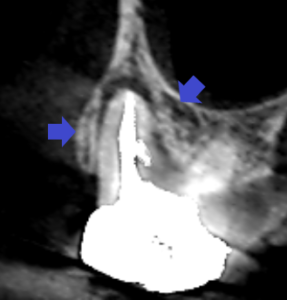

上顎大臼歯の近心頬側根の冠状断のCT画像です。

矢印の先に近心頬側根をとり巻くように大きな膿の影がみられます。

歯根破折を疑わせる画像です。

青い矢印の先がパーフォレーションリペア部です。